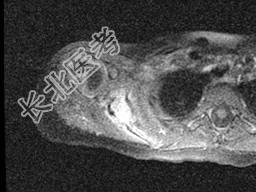

单项选择题女,2岁半, 无痛性右肩部肿块,结合图像, 最可能的诊断是 ( )

A、朗格汉斯细胞增多症

B、尤文肉瘤

C、骨髓瘤

D、霍奇金病

E、淋巴瘤